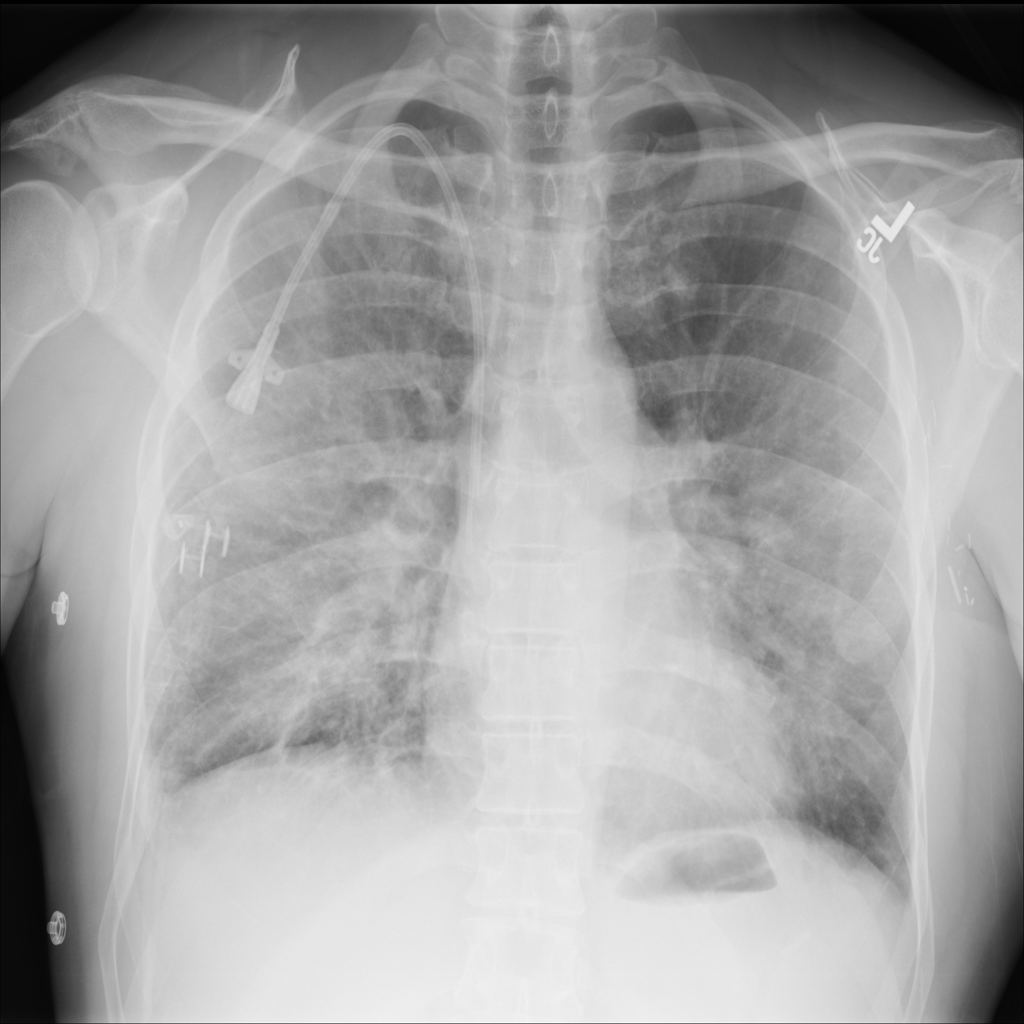

PAT-A1E2 · IMG-001Pneumonia

PAT-A1E2 · IMG-001

AP